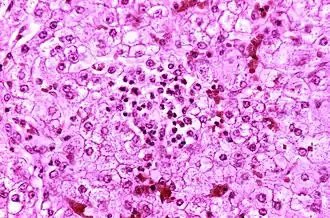

Description de l'image Reye's syndrome liver-histology.jpg.

La maladie provoque une stéatose hépatique avec une inflammation minimale et une encéphalopathie sévère (avec gonflement du cerveau). L'ictère n'est pas habituellement présent. Le foie peut devenir légèrement agrandi et ferme, et l'apparence des reins se modifie.